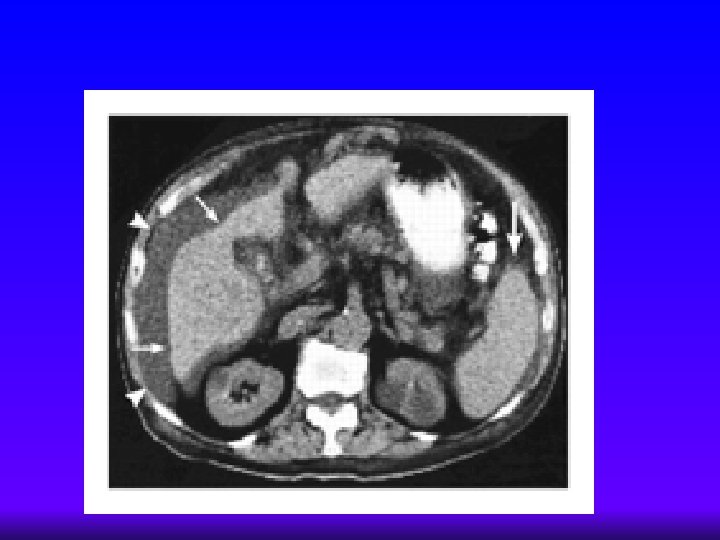

¿En quién sospechar cirrosis? Cirrosis hepática ¨ TAC – No de rutina, excepto ante la sospecha de hepatocarcinoma – Densidad heterogénea, esteatosis, hipodensidad – Visualización del trombo en la porta – Menos sensible y específico que el US en la evaluación de Hipertensión portal ¨ Arteriografía – Evaluación anatómica pretransplante – Evaluación de hepatocarcinoma